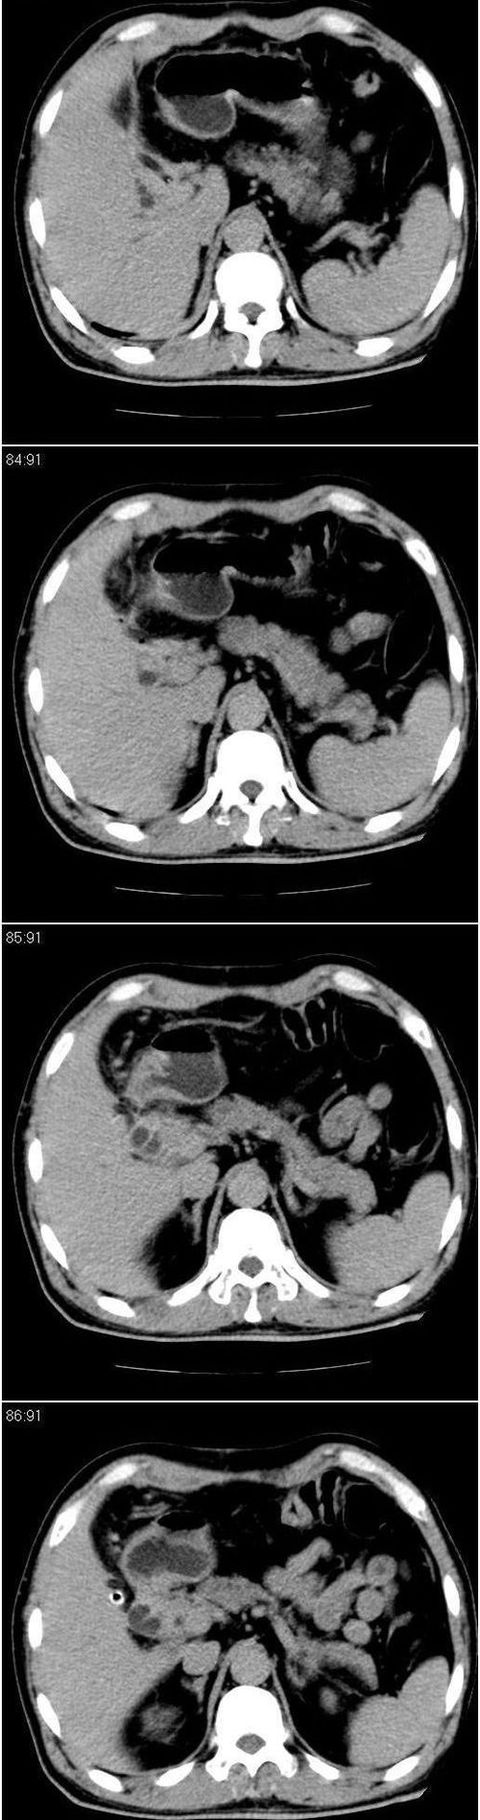

标题: CT13147:男,57岁。因胆结石阻塞性黄疸入院。 [打印本页]

标题: CT13147:男,57岁。因胆结石阻塞性黄疸入院。

男,57岁。因胆结石阻塞性黄疸入院。这是胆囊切除术后的照片,看看此片到底有什么问题。

胆总管有没有问题,尤其是肝门附近的胆总管?

肝门附近的胆总管轻度扩张 请楼主复习术前片

肝内外胆管轻度扩张,胆囊窝内见引流管考虑胆囊切除术后改变.胃窦部软组织似增厚,建议胃镜检查.

在手术切除胆囊的过程中,发现肝门部胆总管恶性占位,因为家属不同意手术,没有切除,能看出来么?

现有资料很难说,薄层可能清楚些,如临床不提供,易诊断为术后改变。

不是楼主提醒还真看不出来,肝内胆管扩张。略显僵硬。

肝内外胆管轻度扩张。楼主提示左右肝管合汇区域壁稍厚。胆总管末段壁似也稍厚有轻度强化。就现有资料诊断难。